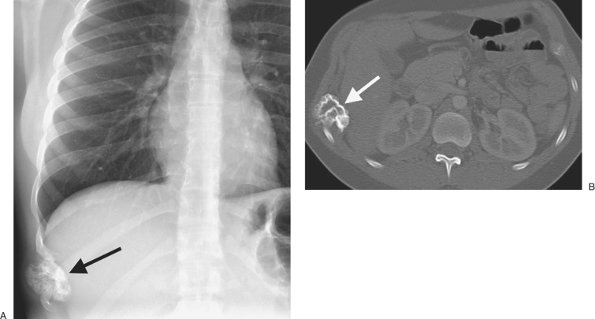

15 years. The plaques involve mainly the posterior and anterolateral aspects of the pleura, following the contours of the posterolateral seventh to 10th ribs, and the domes of the hemidiaphragms, and spare the lung apices and costophrenic angles. They almost always involve only the parietal pleura but occasionally may be seen in the visceral pleura in the interlobar fissures and sometimes involve the pericardium (Fig. 9-31). On chest radiographs, pleural plaques are unilateral in approximately 25% of cases (33), although more plaques are detected on CT than chest radiography. Pleural plaques are not premalignant, but detection of them is important for three main reasons: (i) in patients with associated interstitial lung disease, the presence of pleural plaques, in the appropriate clinical setting, strongly suggests the diagnosis of asbestosis; (ii) they are virtually pathognomonic of asbestos exposure and should prompt an occupational history; and (iii) they may encourage a patient to stop smoking, because there is a synergistic interaction between asbestos exposure and smoking in the development of lung cancer. Asbestos-related pleural disease has five manifestations: (i) pleural plaque with or without calcification, (ii) asbestos-related pleural effusion, (iii) diffuse pleural thickening, (iv) rounded atelectasis, and (v) mesothelioma.

FIGURE 9-30. Old tuberculous empyema. A: PA chest radiograph shows dense calcification throughout the right hemithorax. B: Chest radiograph with dual energy, to emphasize the bones and calcium, optimally shows the long linear calcifications in the right hemithorax. C: CT shows dense pleural calcifications (arrows) involving only the right hemithorax, associated with loss of lung volume. [AU/PRODUCTION: Note that 9-30B should be a chest radiograph; what is labeled as 9-30B appears to in fact be 9-30C, and 9-30B is missing.]